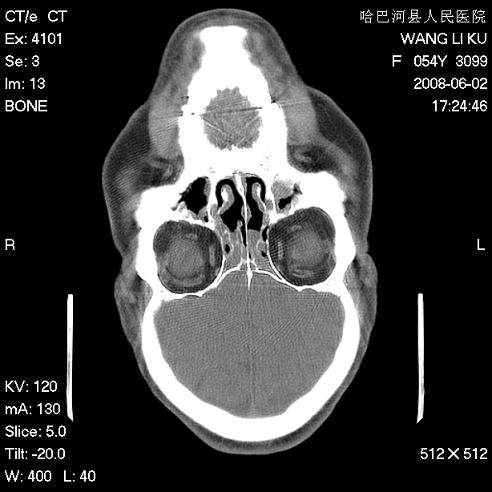

标题: CT13803:反复性鼻塞、流涕一年余 [打印本页]

标题: CT13803:反复性鼻塞、流涕一年余

副鼻窦炎,右上额窦积脓。左眼肌锥内见致密影,视神經受压

1.全组副鼻窦炎2.双侧上颌窦积液

全组副鼻窦炎 肌锥内高密度灶。建议进一步检察检查

1、全组副鼻窦炎。

2、左眼眶肌锥内病变,小血管瘤?建议增强。

1)全副鼻窦炎(左侧上颌窦黏膜下囊肿或息肉)。2)左眼眶肌锥内不规则小结节状软组织密度影;考虑为小血管瘤可能。建议行ct增强扫描检查。

全组副鼻窦炎,左侧肌锥内不规则形软组织肿块影,与眼外肌密度相当,左侧视神经受压,肿块与视神经及眼外肌分界清晰,眼外肌无增粗,眶壁无破坏,球后脂肪间隙不模糊,考虑良性改变,小血管瘤或神经源性肿瘤可能,建议增强扫描。

谢谢,增强扫描做了,眶内病灶与海绵窦同步明显强化,血管瘤